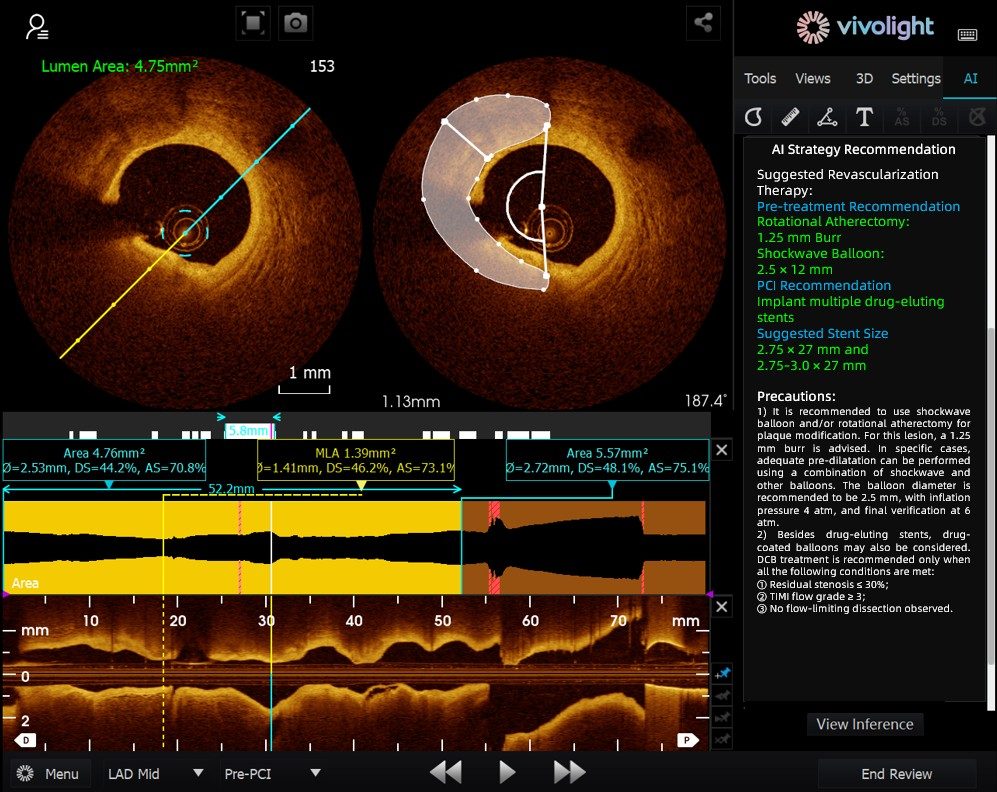

Developed based on Vivolight Medical’s OCT system, the AI-OCT is a next-generation intelligent decision-support system for intravascular imaging. It integrates scattered intravascular imaging diagnostic data—including lumen diameter, culprit lesions, OCT-FFR, and plaque natures—into comprehensive treatment strategies and actionable recommendations. As an independent research software embedded in the OCT platform, it is co-developed with various hospitals to create customized versions tailored to specific clinical needs.

During the cutting-edge forum, experts emphasized that AI-OCT System represents a transformative shift from "viewing images" to "delivering treatment plans"—addressing the challenges of information overload and complex decision-making in cardiac interventional procedures, which traditionally rely heavily on physician experience. Key advantages of the system include:

● Real-time Intraoperative Guidance: It dynamically organizes diagnostic information during surgery, providing key metrics and clinical recommendations.

● Evidence-based Decision-Making: All suggestions align with expert consensus and clinical guidelines, ensuring rigor and reliability.

The AI-OCT System adopts a "small model + big data + large model" architecture: small models enable precise image interpretation, while large models drive comprehensive clinical reasoning. Leveraging high-quality cardiovascular databases and Retrieval-Augmented Generation (RAG) technology, it delivers end-to-end support from lesion assessment to treatment strategy development.